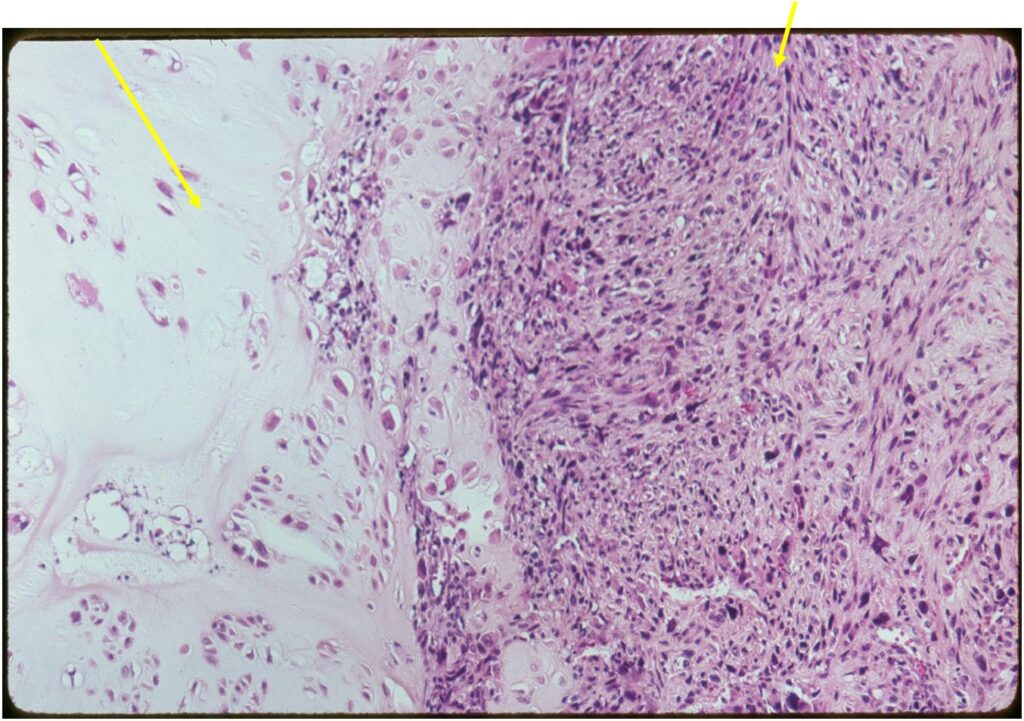

Junction of cartilaginous and noncartilaginous components is sharp and distinct. There are no dedifferentiated areas admixed in the middle of the cartilaginous areas

(Right Arrow) Dedifferentiated Component

(Right Arrow) Spindle Cell Component

(Top Arrow) High Grade Dedifferentiated Spindle Cell Sarcoma Component

(Left Arrow) Low Grade Cartilage Component

(Right Arrow) Low Grade Cartilage Component